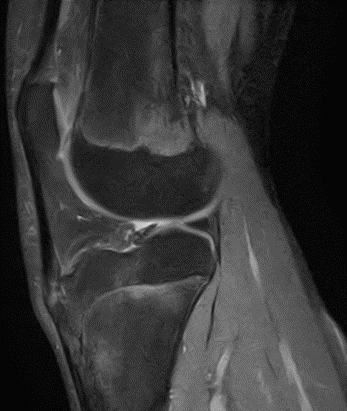

MRIで見つかったOsgood-Schlatter病 2026年3月2日 症例,靱帯、神経病変(Ligament and nerve lesions) みなさんこんにちは。 ブログ担当技師です。 今回はOsgood-Sc… 続きを読む